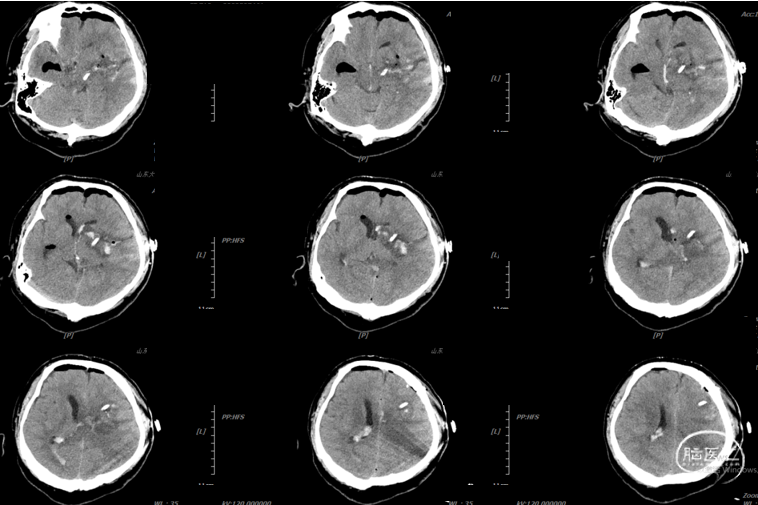

辅助检查:头胸部CT平扫2026-03-14我院脑出血并破入脑室,请结合临床复查,蛛网膜下腔出血。双肺少许纤维灶,双肺坠积性改变,请结合临床隔期复查,双肺少许小结节,考虑低危结节可能,建议结合临床年度随诊复查双肺部分小叶间隔增厚,肺水肿不除外,建议结合临床短期复查,冠脉壁钙化灶,胆囊结石。头颈部CTA2026-03-14我院颅内动脉轻度粥样硬化性改变,左侧优势型椎动脉,椎基底动脉迂曲延长。

2026.3.14术后即刻: